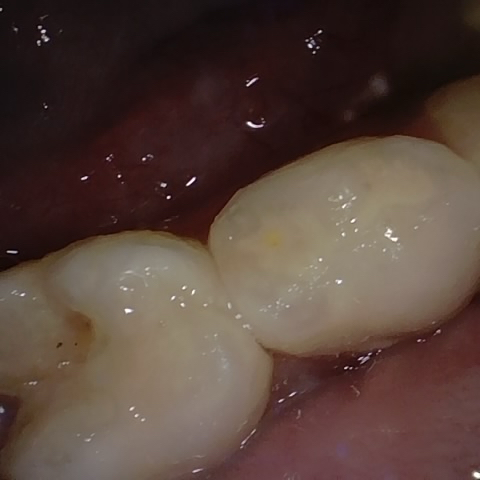

Annotated as "Good"